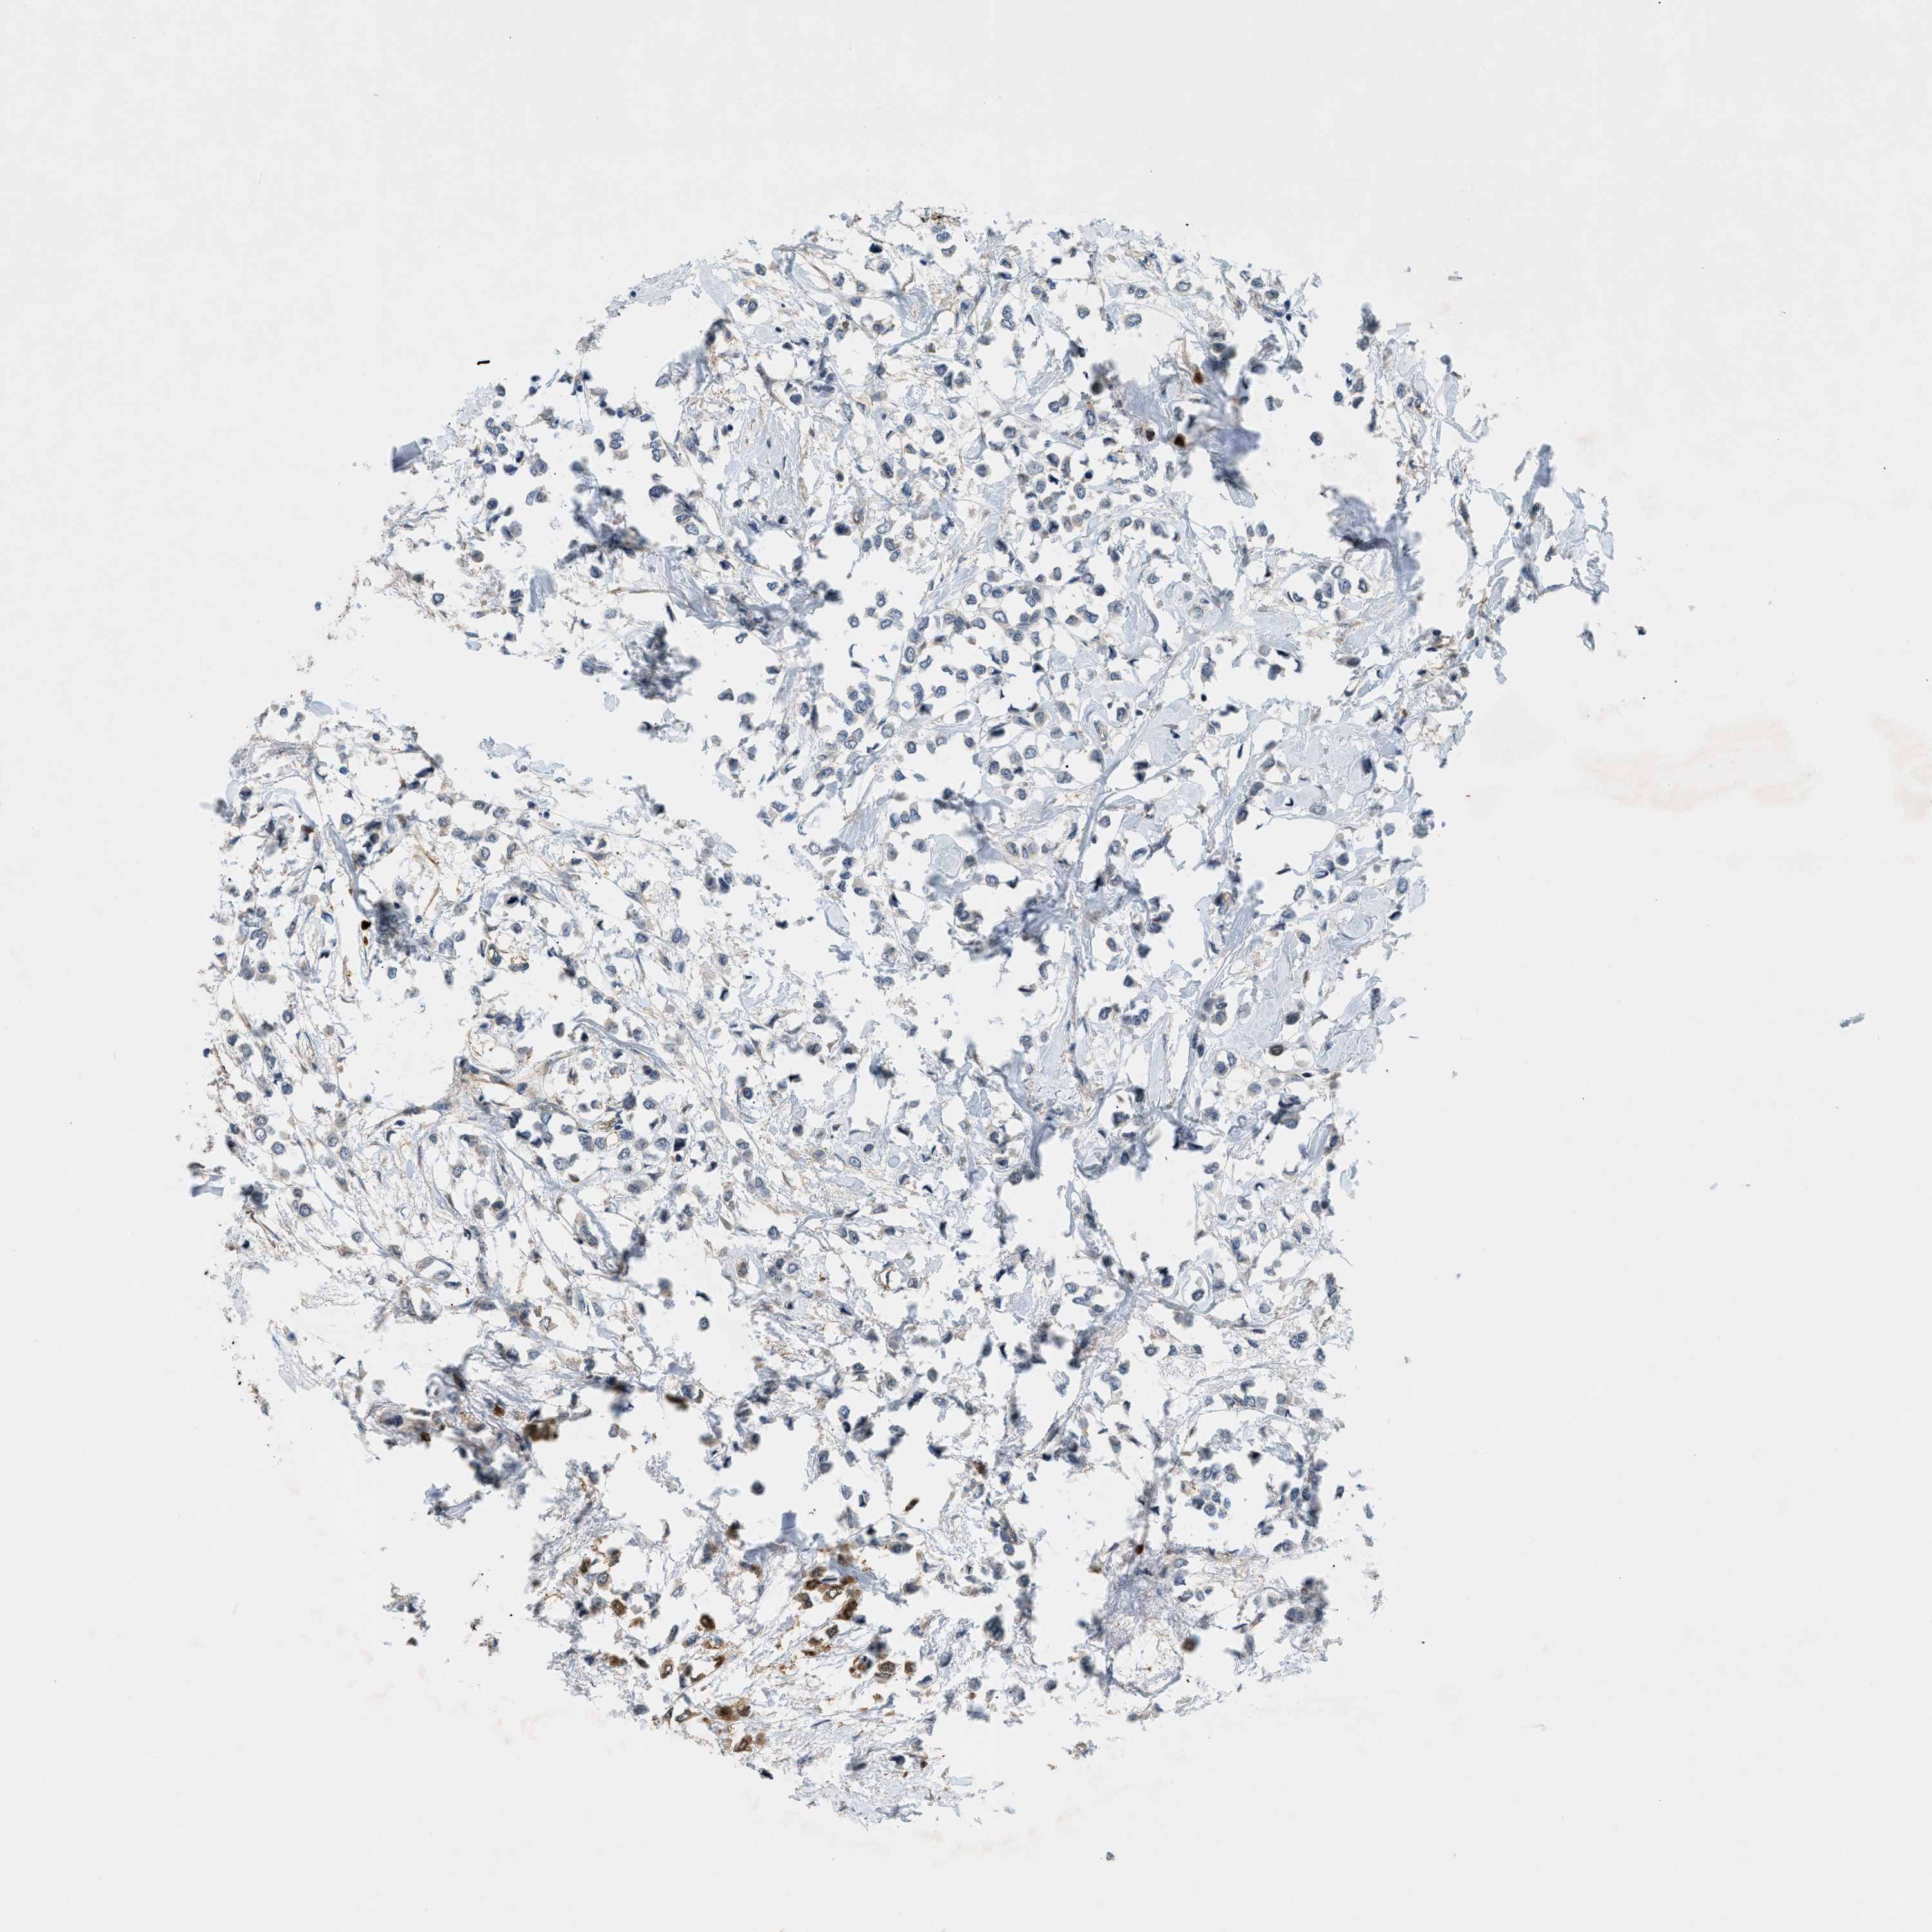

CANCER BREAST CANCER Show tissue menu

BRCA TCGA BRCA VALIDATION PROTEIN EXPRESSION